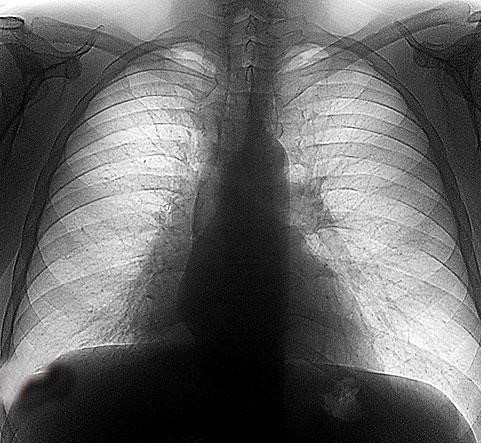

ДИАГНОСТИКА ПРИ РАКЕ ЛЕГКОГО

Рентгенологическое исследование — один из основных методов диагностики опухолей лёгкого, благодаря которому у 80% больных можно выявить заболевание, предположить характер опухоли, определить её распространённость, оценить состояние внутригрудных лимфатических узлов.

Все рентгенологические данные необходимо рассматривать в сочетании с результатами детального клинического обследования и других методов диагностики (КТ, МРТ, эндоскопического, хирургического и др.).